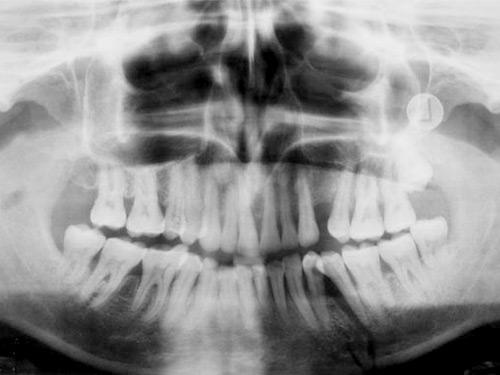

Para reconstruir el maxilar inferior que está fracturado

Afortunadamente, el pitón del toro de José Julián Llaguno no seccionó la carótida, como se pensó en un principio, sino que se trata de una cornada en el cuello que entró por debajo del maxilar inferior fracturándolo. El pitón lesionó la carótina externa y siguió su trayectoria hacia la órbita del ojo izquierdo, lo que provocó un profuso sangrado.

En esta segunda intervención a la que será sometido, los médicos que le atienden van a reconstruir el maxilar fracturado y otras lesiones internas que provocó el pitón.